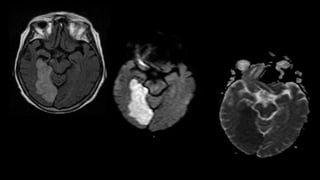

HEMORRHAGIC

TRANSFORMATI

ON

T1WI T2WI

SWI

PHASE

• #91 Sagital T1 and axial T2 wi showing areas of altered signal intensity appearing heterogeneously hypointense with hyperintense foci within on T1 and ,Heterogenously hypERintense on T2 in left frontoparietal lobe with loss of grey white matter differenciation

• #92 FLAIR also shows high signal intensity

• #93 Showing few areas of restricted diffusion in the periphery on DWI and ADC

• #94 Extensive blooming is also seen within APPEARING white on phase images s/o large subacute infarct withj hemoorhagic transformation